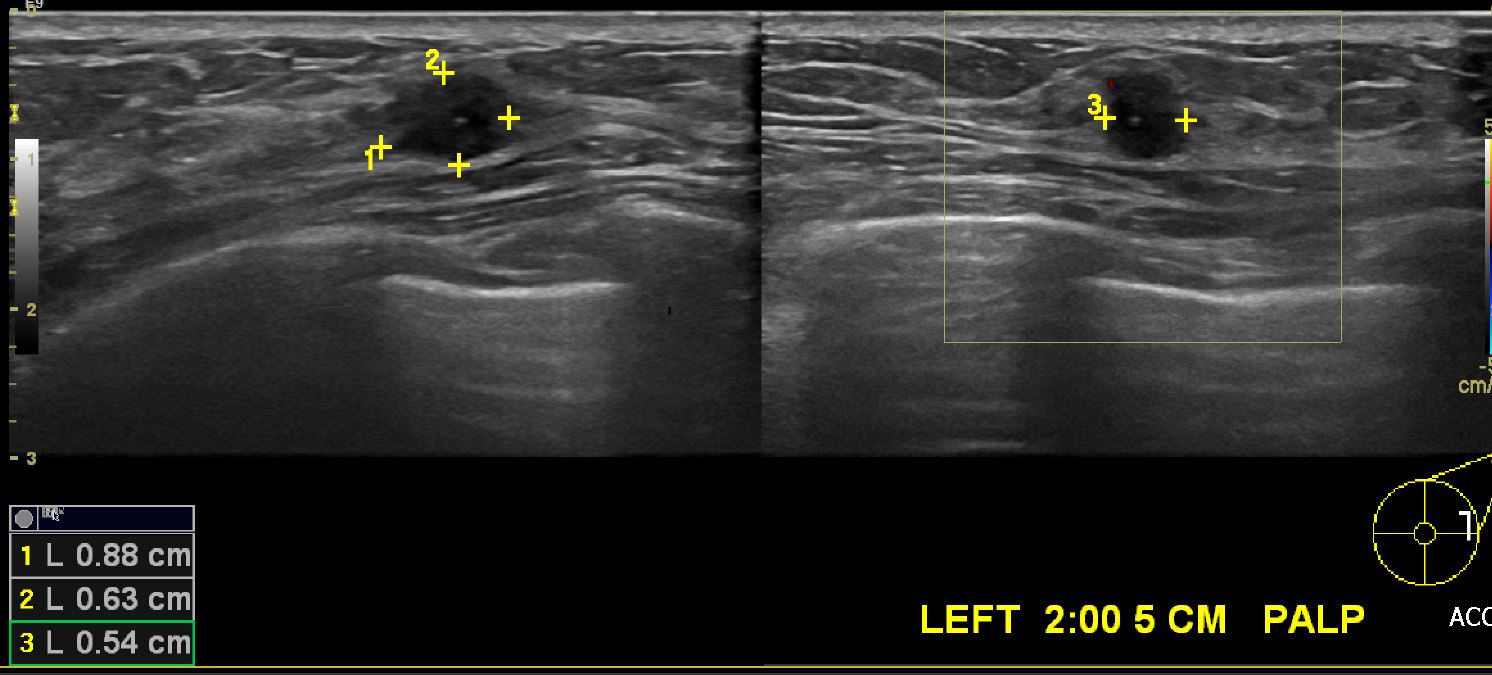

2달전 만져지는 멍울있어 내원하신 50세 여자환자로 유방초음파후,좌측유방 2시방향으로

5cm떨어진곳을 조직검사하여 침윤성 유관암 진단되셨습니다.